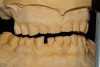

Figure 1  Accurate casts mounted at arbitrary OVD.

Figure 1